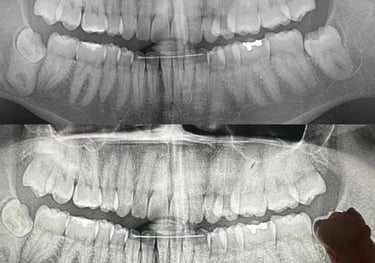

Endodoncia

La endodoncia es un procedimiento dental que consiste en eliminar la pulpa infectada o inflamada del interior del diente para salvarlo y evitar su extracción. Es una solución efectiva para aliviar el dolor, eliminar infecciones y restaurar la funcionalidad de la pieza dental. En nuestra clínica, realizamos tratamientos de endodoncia con tecnología de vanguardia y máxima comodidad, asegurando una recuperación rápida y resultados duraderos. Confía en nosotros para cuidar tu salud bucal y devolverle la vida a tu sonrisa.